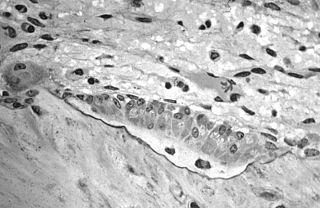

Light micrograph of osteoid, containing two osteocytes, being synthesized by osteoblasts.

In histology, osteoid is the unmineralized, organic portion of the bone matrix that forms prior to the maturation of bone tissue.[1] Osteoblasts begin the process of forming bone tissue by secreting the osteoid as several specific proteins. When the osteoid becomes mineralized, it and the adjacent bone cells have developed into new bone tissue.